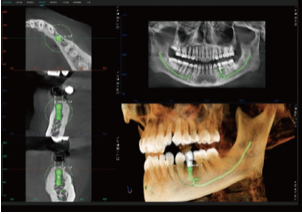

Simulação de Extração Dentária e Óssea – Planeamento de Implante Imediato

Permite a extração do dente comprometido e a sua substituição por um implante adequado na simulação.

Melhora a comunicação entre médico e paciente, permitindo ao paciente visualizar o resultado final do implante antes da extração.